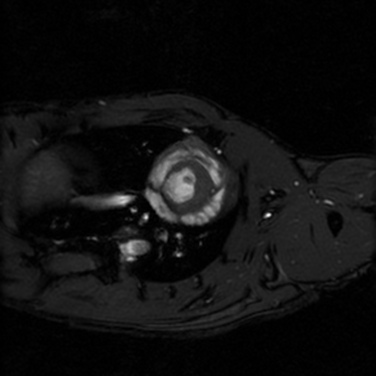

- Kardiyak görüntüleme

Kardiyak Görüntüleme

Kısa eksen, uzun eksen ve dört odacık kardiyak görüntüler prospektif tetikleme ile veya retrospektif olarak elde edilebilir.